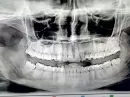

Мне в детстве удалили клык слева, соответственно зубы сместились влево. На нижней челюсти скученность зубов.

Одни ортодонты советуют удалить все зубы мудрости, выровнять центр и поставить имплант на место клыка, а другие, что можно ничего не удалять, просто переместить 4-ку на место удаленного клыка, но центр не выравнивать.

Решение Вашей проблемы требует комплексного подхода. Для восстановления срединной линии на верхней челюсти целесообразнее было бы удалить клык справа и за счет образовавшегося места сместить фронтальную группу зубов вправо, соответственно и все остальные зубы верхней челюсти потребуется сместить для предотвращения возникновения трем.

Верхние зубы мудрости целесообразнее удалить, так как мы точно будем удалять нижние зубы мудрости (далее поясню), а без антагонистов они не будут выполнять своей функции.

Касаемо нижней челюсти - скученность зубов образуется из-за недостатка места в зубном ряду, как раз таки здесь можно удалить зубы мудрости, чтобы за счет них появилось больше места.